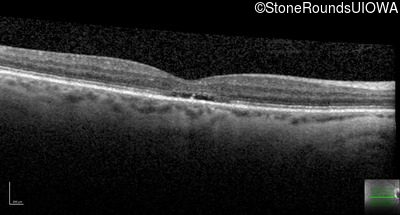

Age at visit: 55 years

OD OS

This 30 year old man has had reduced acuity and abnormal color vision OU since early childhood.

The clinical features supporting the diagnosis of blue cone monochromacy in this patient include: stable reduced acuity, photophobia and very poor color vision since early childhood, a normal fundus appearance, normally sighted parents and three similarly affected male relatives on the maternal side of his family.